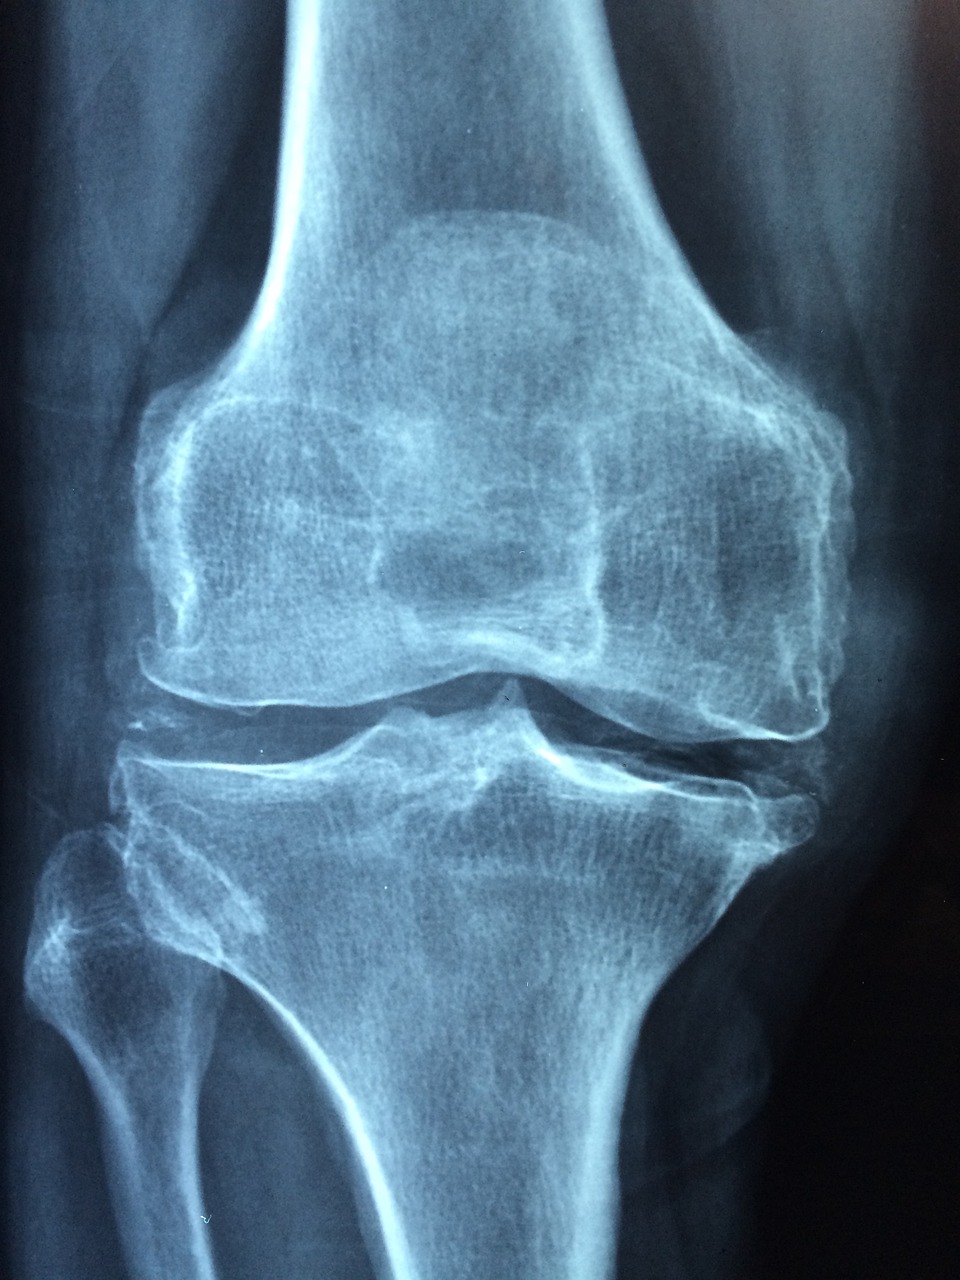

4. 신성 골이영양증 (Renal Osteodystrophy)

증상

만성 PTH 불균형으로 발생하는 뼈 질환.

뼈 통증, 골절 위험 증가, 성장 지연(소아의 경우).

장기적으로 기형적인 골 구조로 발전할 수 있음.